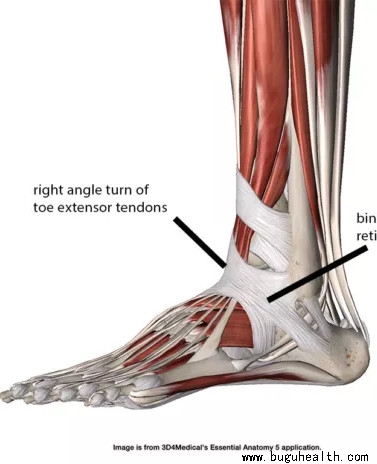

- 布骨医学科普:足背伸肌支持带与鞋带叮咬症 布骨康复医疗中心 ,2021-09-14

- 人体肌腱结构中有一个独特的机械特性就是在许多关节附近存在支持带(retinaculum)。这是一种带状或膜状结构将器官或者部分器官固定在某个位置。该结构通常表现为肢体远端的深筋膜变厚并在肌肉收缩时将肌腱固定于某一位置(图1)。 .....